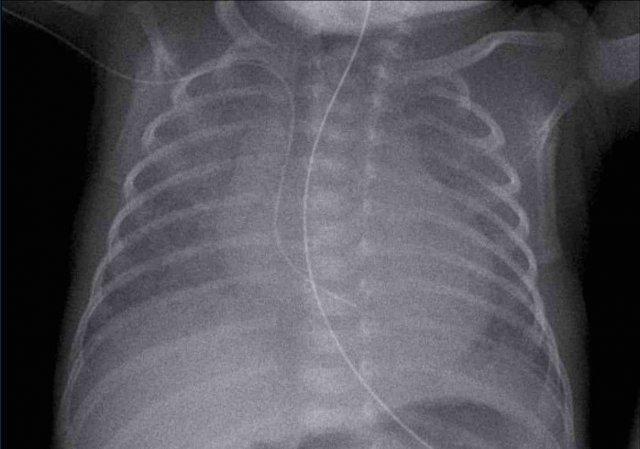

33 tuần + 5 tuần tuổi thai, ngày đầu tiên.

Nhìn vào hình ảnh trước.

Những phát hiện là gì?

Findings:

- Intubated

patient. - Good position of endotracheal tube (ETT). Hyperinflation.

- Symmetric

granular opacifications with air bronchograms. - Definition of heart and vessels

is diminished.

This is a typical case of RDS.